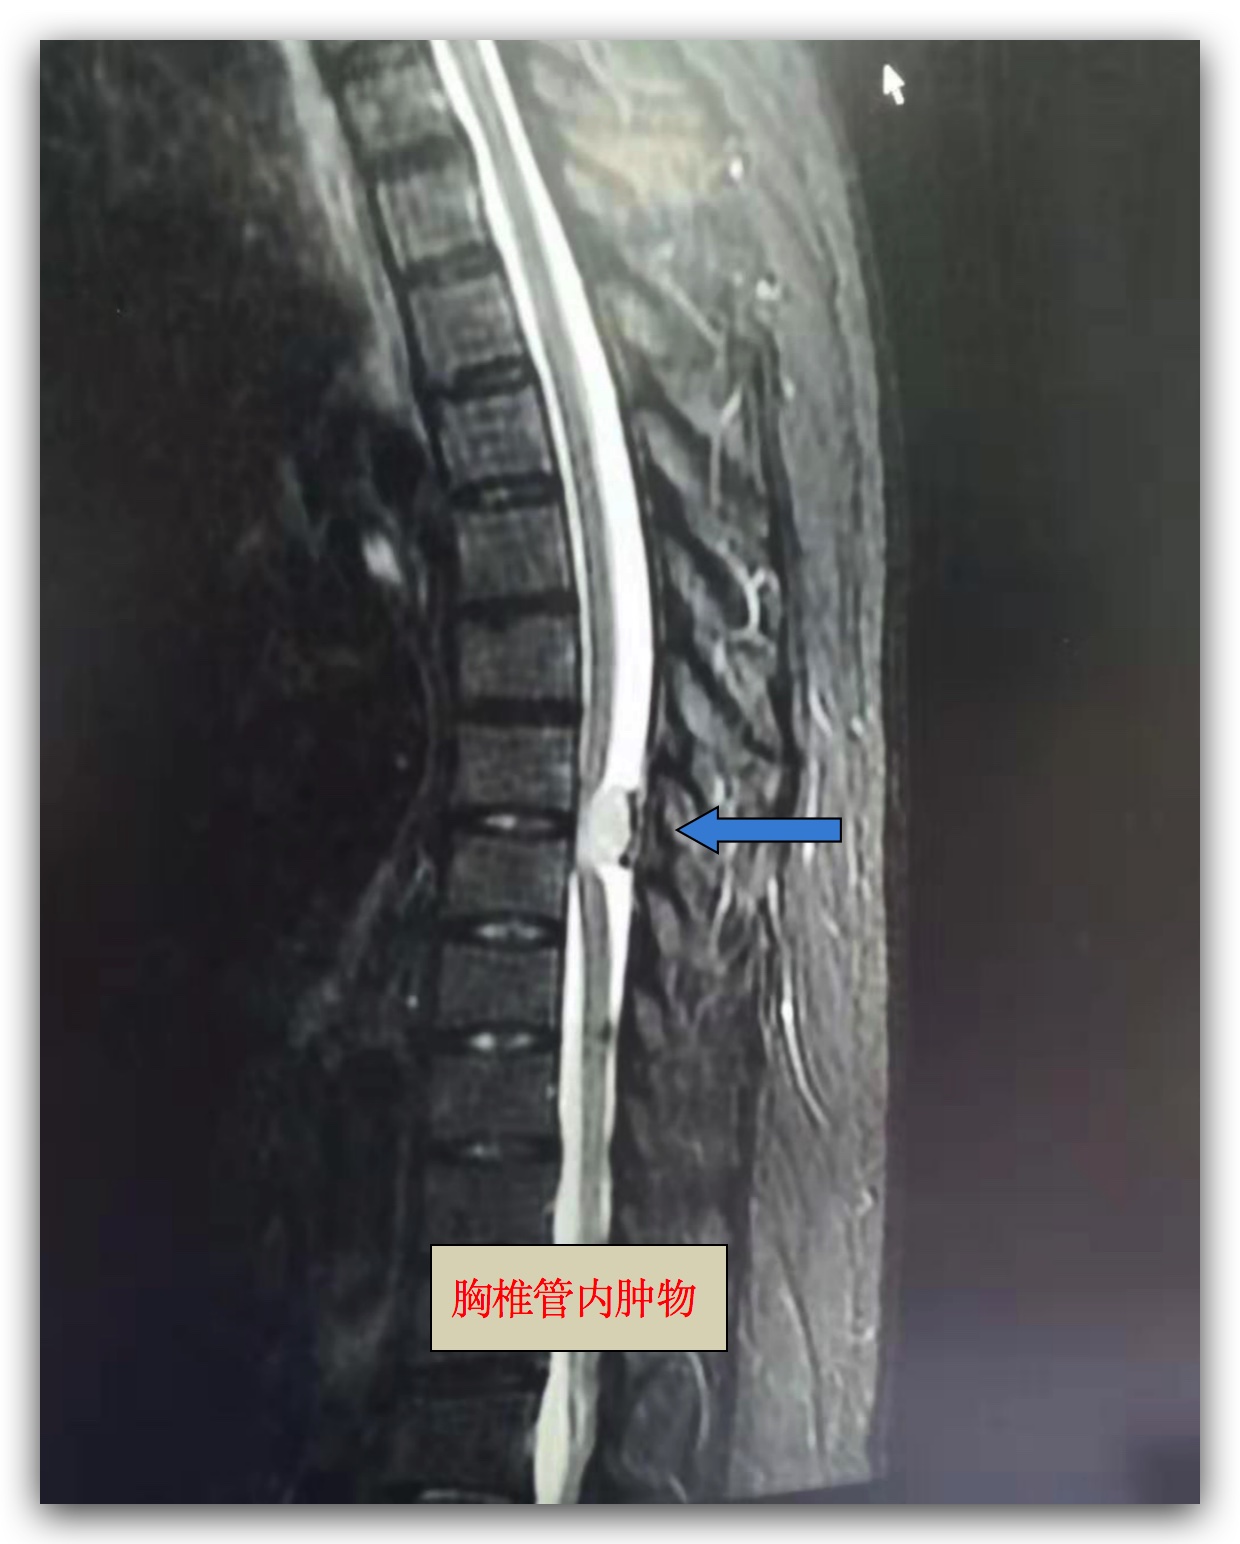

案例一:

胸椎管内占位

患者赵女士,60岁,双下肢麻木无力渐进性加重半年,长期药物治疗无效,胸部于脐平面以下皮肤浅感觉障碍,双下肢肌力减退,肌张力增高,于6月14日入院治疗。经完善相关检查,明确诊断示:胸椎管内占位,考虑脊膜瘤、颈椎间盘突出症、颈椎管狭窄、高血压病, 经过反复查体明确责任节段为胸7-8节段椎管内的占位病变, 手术指征明确,无明显手术禁忌症。科主任卜祥鹏、副主任医师李秀春积极讨论手术方案,于6月27日为患者施行肿瘤切除术,术中应用魔钻切除椎板,应用神经剥离子游离瘤体并完整切除,术后患者双下肢活动正常,无缺血再灌注并发症,术后延长引流管留置时间,密切观察脑脊液漏的恢复情况,并配合药物治疗,患者下肢麻木、无力得到一定程度的缓解,因为肿瘤压迫时间长,神经功能的继续恢复需要更长时间,医护人员将继续给予患者长期随访、追踪治疗。